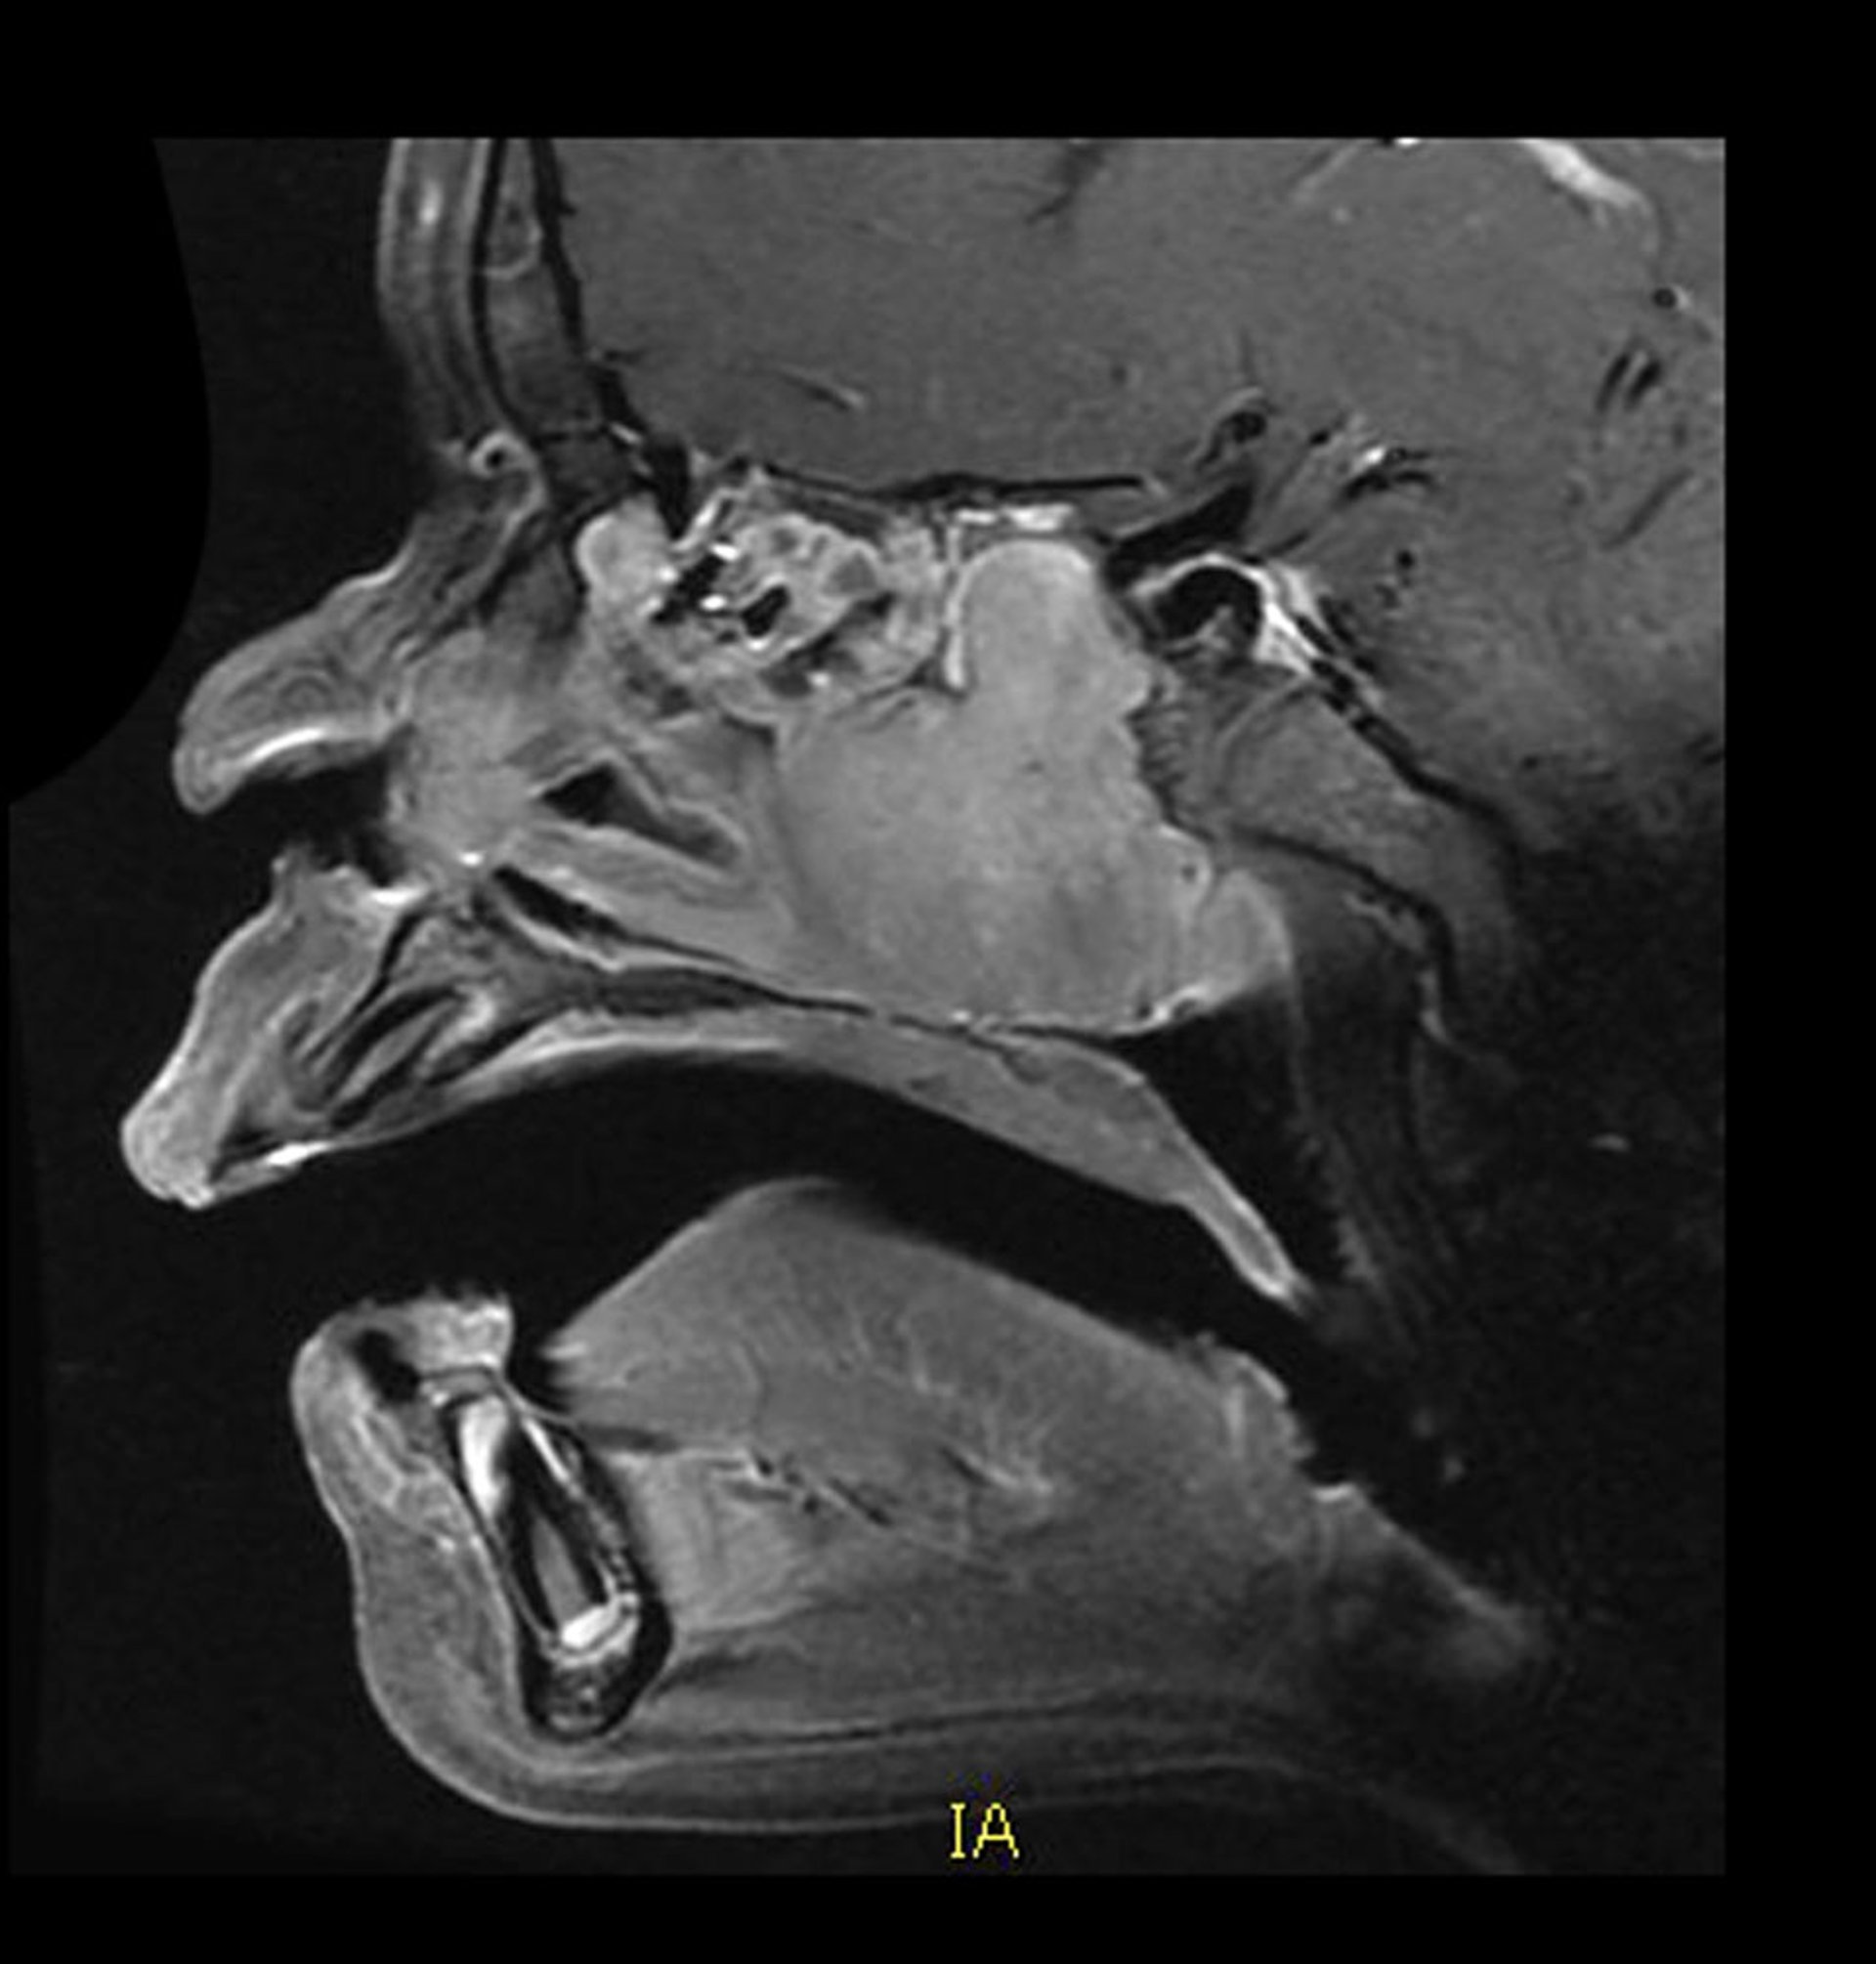

Diagnosis of juvenile angiofibromas usually requires CT and MRI.

Angiography is often done so that the tumor vessels can be embolized before surgery.